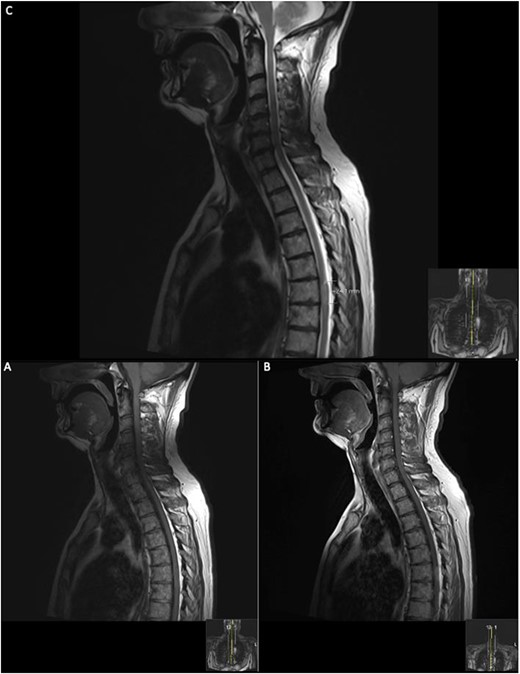

On the second day post-operatively, the patient gained 4/5 power in his hips, knees and right ankle and gained 3/5 power in his left ankle. The patient’s urinary catheter was removed 10 days post-operatively. A post-operative MRI was performed after 19 days showing GTR of the lesion (Fig. 3).

19 days post operative MRI; T1 pre-contrast sagittal (A) and T1 pre-contrast axial (B) show evidence of surgery at T6. Post-contrast T1 sagittal (C) and axial (D) show evidence of a small ‘fleck’ of dural enhancement, however, provide no evidence of any definite residual lesion.